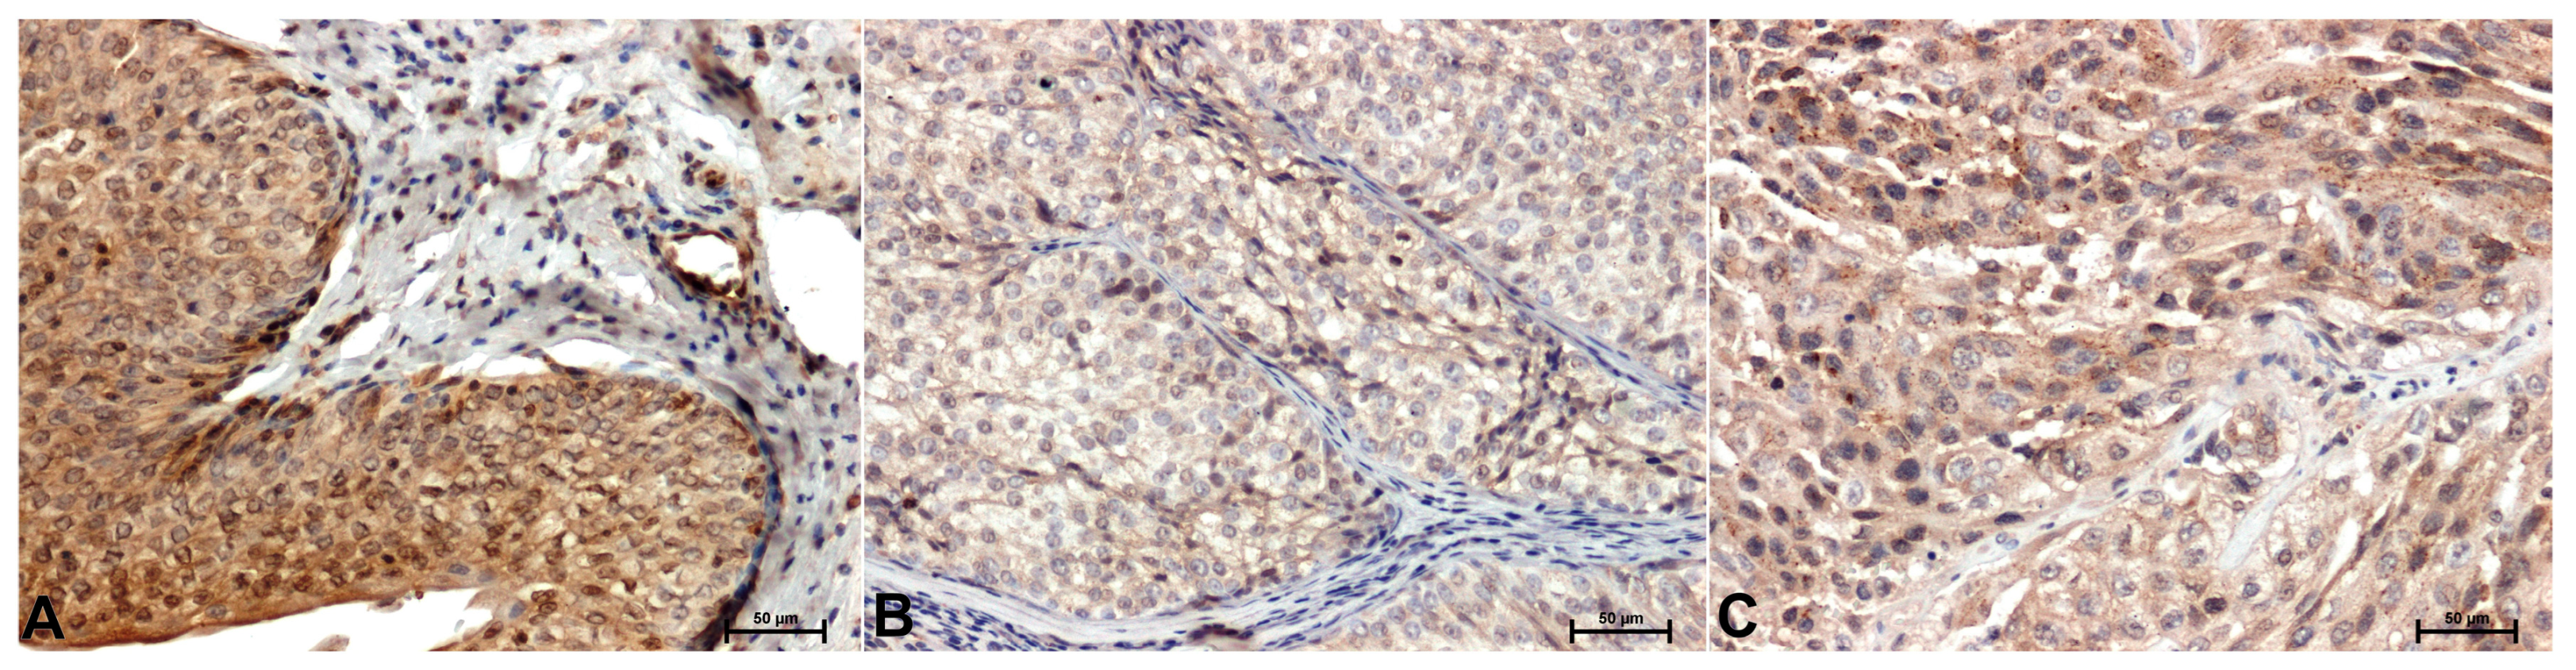

| CacyBP/SIP | 71.14 ± 1.37 | 108.87 ± 1.59* | 145.76 ± 1.21* |

| ERK1/2 | 120.04 ± 1.93 | 91.28 ± 1.16* | 121.21 ± 1.08 |

| p38 | 96.81 ± 1.14 | 143.62 ± 1.11* | 159.79 ± 1.22* |